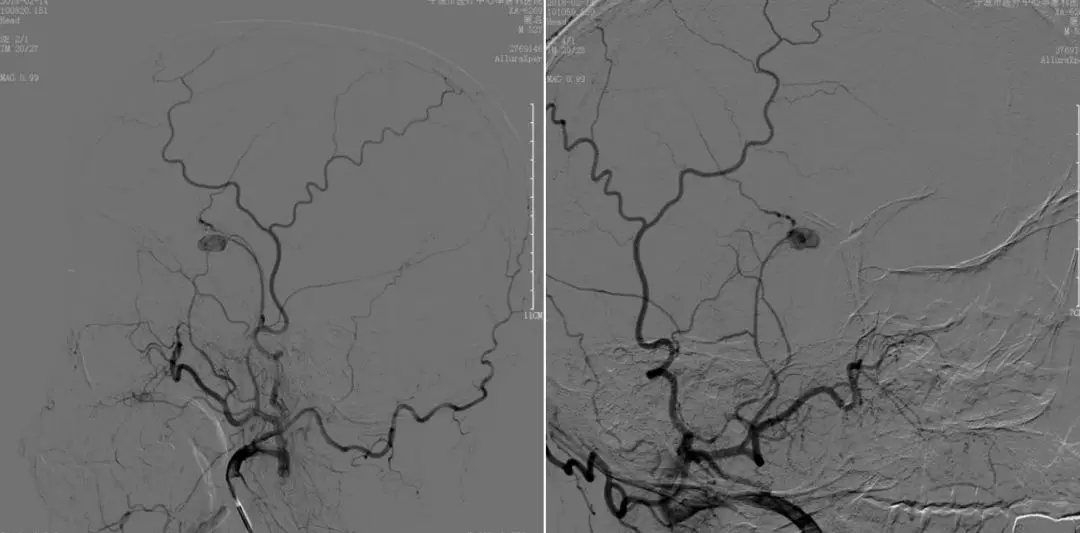

2018-2-13 CTA提示右颞部DAVF可能(图6),建议DSA。仔细阅片CTA未见明显引流静脉,考虑右侧脑膜中动脉假性动脉瘤可能更大。次日行 DSA检查,证实为“右侧脑膜中动脉假性动脉瘤”(图7)。当日即行“右侧翼点入路,脑膜中动脉假性动脉瘤切除加血肿清除术”(图8)。病理回报:镜下纤维细胞增生,可见血凝块伴机化(图9)。2018-2-27 复查CTA提示右侧脑膜中动脉假性动脉瘤术后改变,未见残余及复发(图10)。

图7. 2018-2-14 DSA提示右侧脑膜中动脉假性动脉瘤。